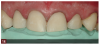

Fig 8. Preoperative photographs were taken as part of the evaluation process, including a close-up view of the maxillary central incisors demonstrating the extent of wear.

Figure 8